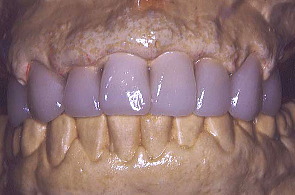

最初の写真は先にワックスで作った形を模倣して口腔内で再現し、仮り歯を作ったもの。次の写真は歯周外科を施し、深い歯周ポケットの歯垢を除去したところ。歯肉の色や艶が健康色を取り戻した。

さっそく私は、グラビアに写っている女性と同じ歯の形を仮り歯で再現した。患者はとても喜んでくれた。また一段と笑顔が綺麗になったように感じた。

口元と上の歯の仮り歯を拡大して撮影したところ。奥のほうの歯は義歯を入れる予定。